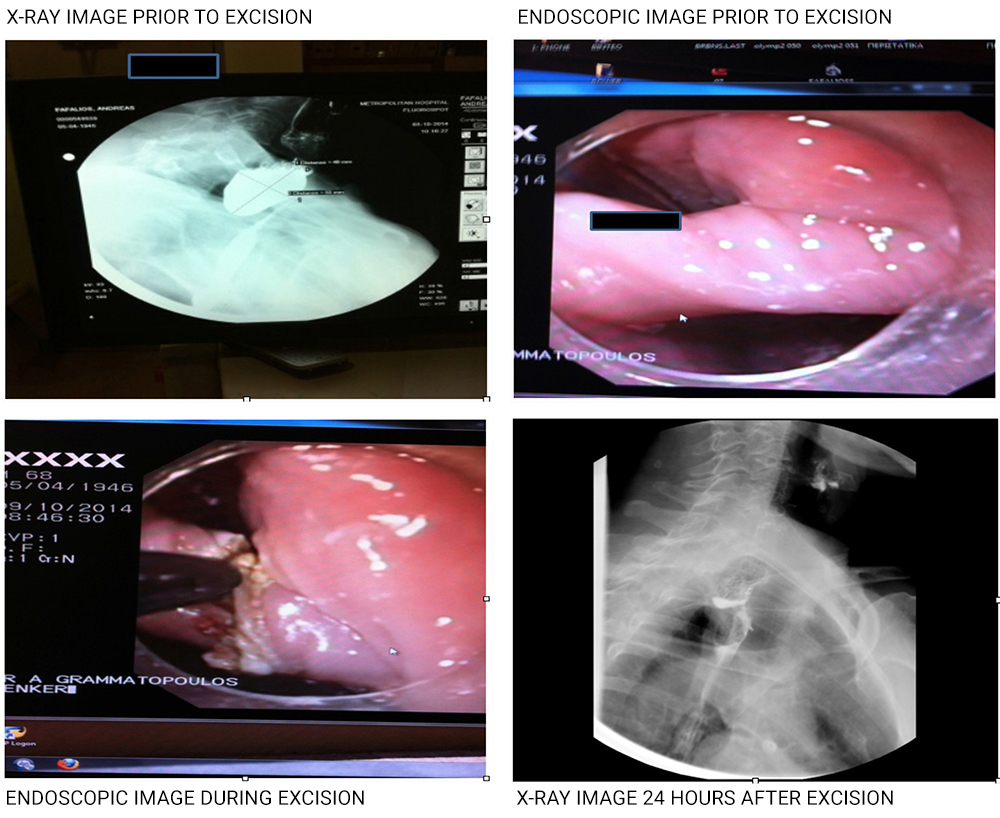

Zenker's diverticulum is a rare diverticulum located behind the upper cardioesophageal sphincter. This diverticulum may be caused by incomplete upper esophageal sphincter relaxation coupled with muscle asynergy in the area. These initially lead to the formation of a small hernia, which eventually develops into a diverticulum. It is more common after the age of 60, predominantly affecting men more than women at a ratio of about 2:1. It may be diagnosed with an esophageal X-ray and requires careful endoscopic examination, as endoscopy specialists cannot easily diagnose it.

Until recently, the treatment of choice was open surgery, followed by long hospitalization and complications. In the last few years, Metropolitan has been using a new, safe and painless endoscopic method, with excellent results and 48-hour hospitalization, and without external incisions on the neck.

The excision is performed under general anesthesia:

A Levin tube is initially placed in the esophagus to preserve the digestive tract and prevent thermal damage to the esophageal walls. A plastic overtube in then placed to isolate the pouch that must be excised (between the diverticulum and the esophagus).

An endoscope fitted with a special lancet is inserted through the overtube and the pouch is slowly excised (starting from the mucosa and moving on to the muscular layer). Once the excision is complete, the incision is sutured with metal clips to avoid mediastinal abscesses and active hemorrhage.

The patient is required to fast for 24 hours and is discharged in 48 hours, provided that the esophagus has been accessed, to rule out emptying (perforation).